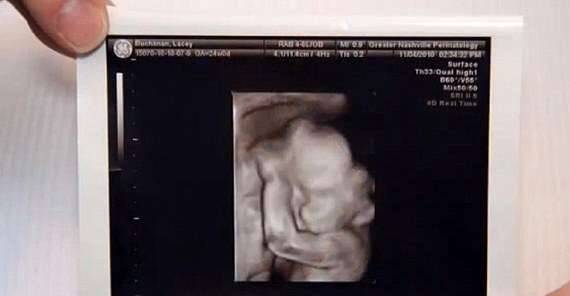

▼Lacey Buchanan是法学院的学生,她15岁时与丈夫Chris Buchanan相遇,两人21岁步入婚姻殿堂。两年后她怀上了宝宝,但产检时的结果却让人心碎。

▼医生告诉他们,这个孩子有羊水带症候群。这种情况非常罕见,孕妇羊膜破裂的话,破裂处会产生一条带状组织,不管它卡在宝宝的哪个部位,都会造成严重的影响。Lacey的宝宝面部被破坏,出生后可能失明。

▼Lacey与Chris心急如焚,最终还是决定将孩子生出来。Christian的情况比他们想像中严重得多,他罹患层齶裂,没有上颚,嘴巴无法闭合,还没有双眼。出生后的前几天,他是在新生儿加护病房度过的。